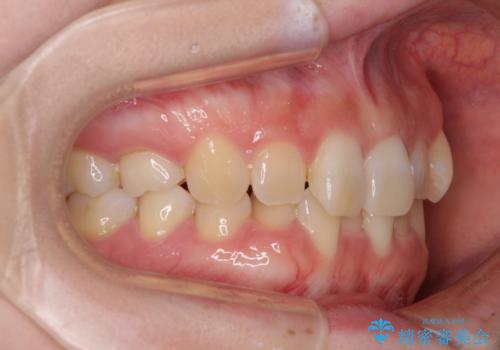

- 前歯のデコボコと強い咬みしめを気にして来院された患者様です。

インビザラインを用いて、前歯の叢生を解消するとともに、ディープバイトを改善していくこととしました。

上顎に乳歯が左右1本ずつ残っていたため、若干咬み合わせに不具合が残りましたが、強い咬合力の原因であったディープバイトをしっかりと改善することができました。